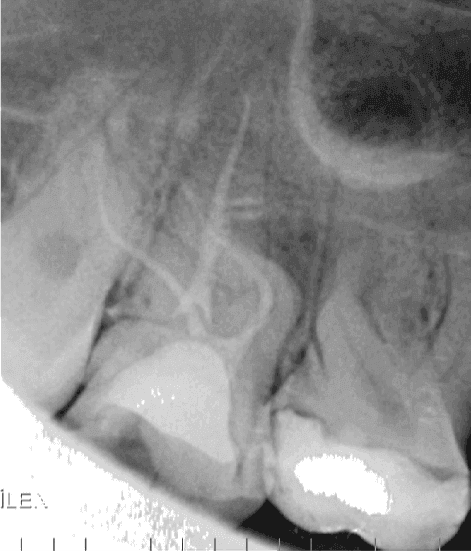

Hastanın klinik muayenesinde 17 numaralı dişte koronal yapıyı ciddi şekilde etkileyen madde kaybı ve kırık hattı gözlemlenmiştir. Alınan pre-operatif periapikal radyografide, kök kanal anatomisinin oldukça kompleks olduğu ve köklerde keskin bir kurvatür bulunduğu tespit edilmiştir. Mevcut koronal harabiyet ve pulpal durum göz önüne alınarak dişe kök kanal tedavisi endikasyonu konulmuştur.

Kanal Dolumu: Şekillendirme ve final irigasyonunu takiben kanallar kurutulmuş ve tek seansta sızdırmaz bir şekilde üç boyutlu obturasyon işlemi gerçekleştirilmiştir. Alınan radyografilerde aşırı kurvatürlü kanalların orijinal anatomisine sadık kalındığı görülmektedir.